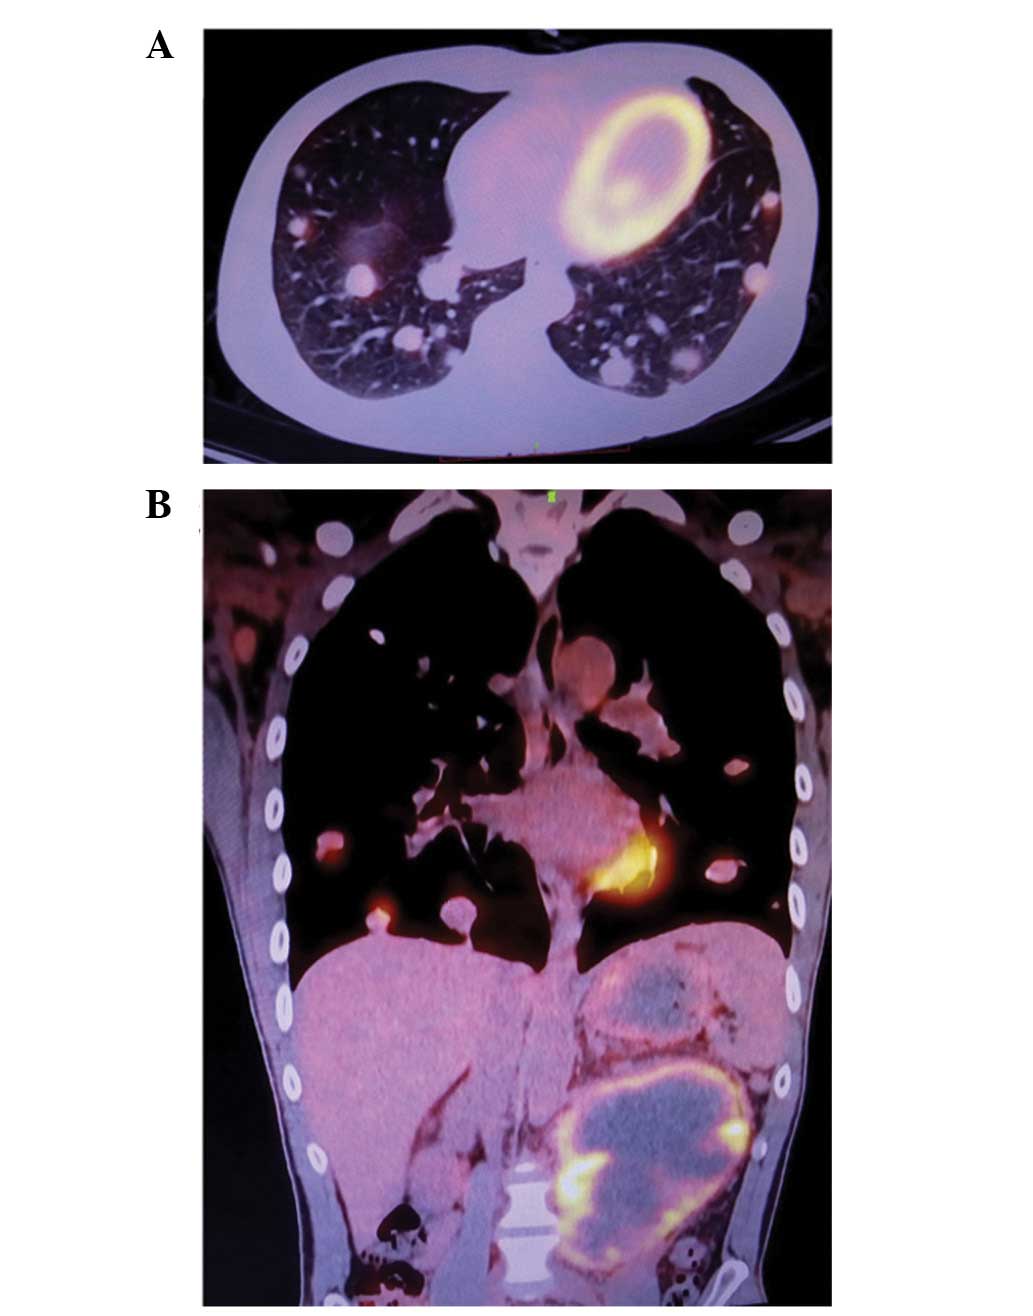

Prior to advanced treatment, fludeoxyglucose F 18 (FDG)-positron emission tomography (PET) assessment was performed in order to evaluate the general condition of the patient and the presence of any distal metastases. FDG-PET indicated the presence of lung and inguinal lymph node metastases, as well as a mass in the abdominal cavity (Fig. 3). The patient was advised to undergo semen cryopreservation, and subsequent cisplatin, etoposide and bleomycin (PEB) combination chemotherapy regimen (20 mg/m2 cisplatin, days 1–5; 100 mg/m2 etoposide, days 1–5; 30 mg bleomycin, days 1, 8 and 15). However, the patient and his family have currently rejected the advice, and the patient did not receive any further therapy.